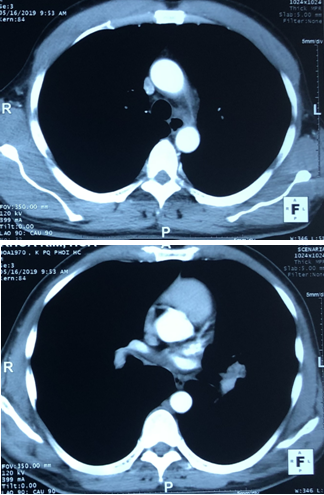

- Chụp PET/CT:

+Hình ảnh khối u phế quản gốc trái 4,6x4,3cm, maxSUV=13,84. Nốt mờ phổi phải 0,7cm, maxSUV=1,99.

+Hạch rốn phổi trải 1,9cm, maxSUV=4,59.

+Hạch trung thất trái 2,8cm, maxSUV=7,75.

Hình 1a: Hình ảnh chụp PET/CT cho thấy khối u phế quản gốc trái 4,6x4,3cm, maxSUV=13,84 (mũi tên vàng).

Hình 1b: Hình ảnh chụp PET/CT cho thấy hạch rốn phổi trải 1,9cm, maxSUV=4,59; Hạch trung thất trái 2,8cm, max SUV=7,75 (mũi tên đỏ).

Hình 1c: Hình ảnh chụp PET/CT cho thấy nốt mờ phổi phải 0,7cm, maxSUV=1,99 (mũi tên xanh).